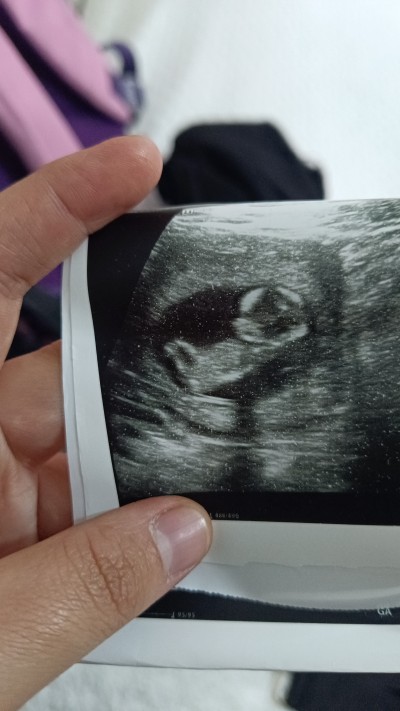

Cinsiyet nedir acaba sizce

Gebelik haftası 13

Kız gibi sağlıkla gelsin ♥️

Kiza benziyo kiz gibi dedi doktor bugun taramada

Kız gıbı bnce kese yuvarlak olunca kız diyorlar ama ne kadar gercek bilmiyorum

Kiza benziyo kiz gbi dedi doktor bencede kizdi hic bacak arasi dolu degildii

Bi tahminim yok ama Allâh gönlünüze göre versin, ultrason halinde bile çok tatlı ya kız bebe tatlılığı var yada çok tatlış bi oğlan sonucu öğrenince bizede yazın 🤗❤🐣

Kiza benziyo kiz gibi dedi doktor kiz gibi sanki demi cunku bacak arasida bomboştuu